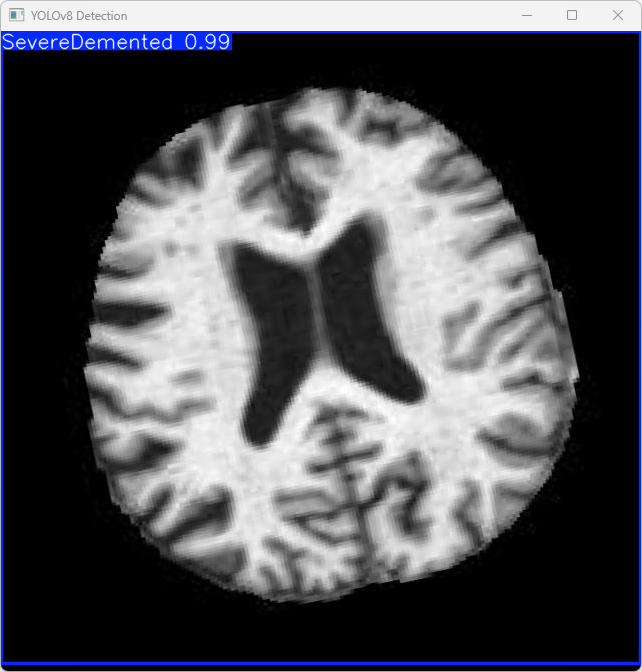

执行imgTest.py代码后,会将执行的结果直接标注在图片上,结果如下:

此段输出源自YOLOv8模型对图片"imagetest.jpg"的具体检测结果。具体数据包括:

图像信息:

(1)处理的图像路径为:TestFiles/imagetest.jpg。

(2)图像尺寸为 640×640 像素。

检测结果:

(1)模型在该图片上检测到 1 个严重痴呆(”1 SevereDemented”)

处理速度:

(1)预处理时间: 14.4 毫秒

(2)推理时间: 5.0 毫秒

(3)后处理时间: 168.1 毫秒

模型在处理图片时具有较高的效率,并且能够成功识别并捕获了1个看屏幕实例,并将捕获的结果保存至指定目录。